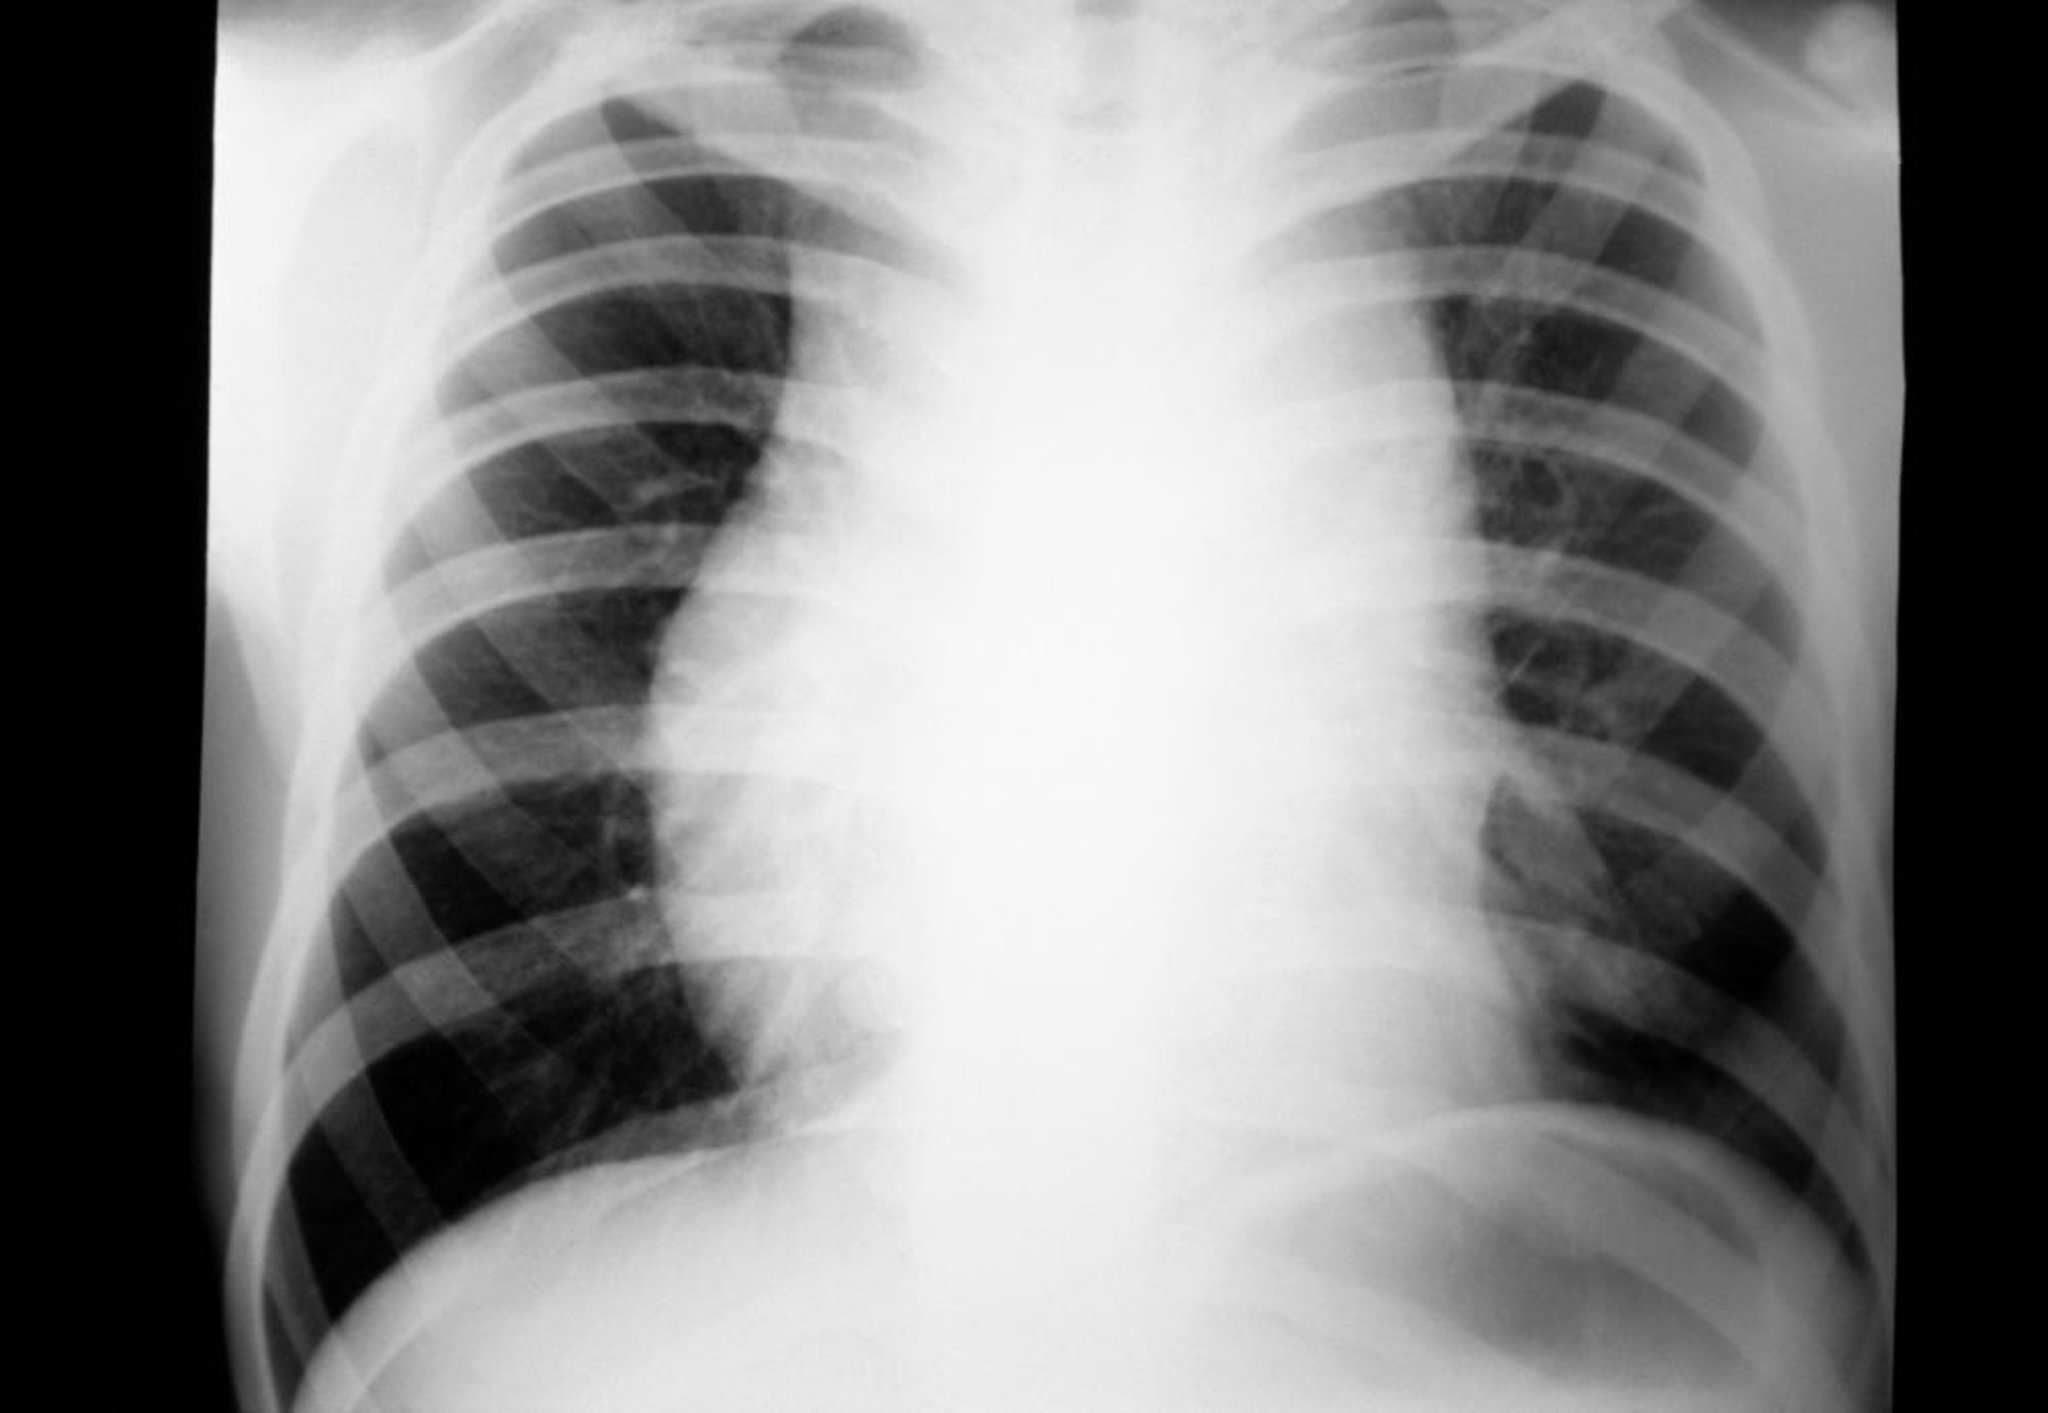

Il linfoma di Hodgkin di solito si sospetta in pazienti che presentano linfoadenopatie non dolenti o adenopatie mediastiniche osservate nel corso di un esame fisico o in una RX torace eseguita di routine (1).

Una linfoadenopatia simile può anche essere determinata da infezioni virali come la mononucleosi infettiva (virus di Epstein-Barr) o l'infezione da cytomegalovirus, la toxoplasmosi, il linfoma non-Hodgkin o la leucemia. Reperti simili sulla RX torace possono derivare da cancro del polmone, sarcoidosi o tubercolosi.

Le anomalie presenti alla RX torace o all'esame obiettivo devono essere confermate con la TC o la PET (positron emission tomography) del torace per scegliere la procedura di biopsia più efficiente. Se solo i linfonodi mediastinici sono aumentati di volume, possono essere indicati mediastinoscopia, chirurgia toracoscopica video-assistita (VATS) o una procedura di Chamberlain (una toracotomia limitata anteriore sinistra, che consente una biopsia dei linfonodi mediastinici, inaccessibili attraverso una mediastinoscopia cervicale). Un'agobiopsia TC-guidata può essere considerata a sua volta; l'aspirazione con ago sottile è spesso inadeguata per la diagnosi del linfoma di Hodgkin.